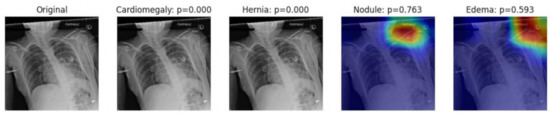

- We trained, validated, and tested the model using pretrained networks and compared the performance of each model using the ROC curves. We visualized the classification decision using Grad-CAM.

2.3. Visualization Using Class Activation Maps

3.4. Visualization